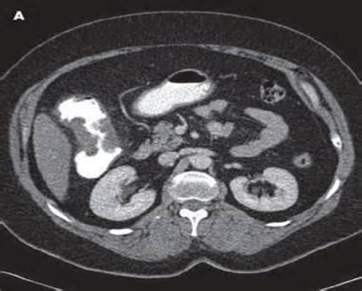

TNM klassifikasiyasında törəmənin divar dəriniliynə invaziyası (T), limfatik düyünlərə yayılma (N) və uzaq metastazlar (M) əsas götürülür (Şəkil 2). Qısaca olaraq:

• 1-ci mərhələdə törəmə əzələ qatını keçmir – T1-2, N0, M0 (5 illik yaşam 90%)

• 2-ci məhələdə törəmə əzələ qatını keçir, ətraf toxumalara keçə bilir, lakin limfa yayılımı yoxdur – T3-4, N0,M0 (5 illik yaşam 60-80%)

• 3-cü mərhələdə limfa düyünlərinə yayılır – T1-4, N1-3, M0(5 illik yaşam 60%)

• 4-cü mərhələdə uzaq metastazlar verir – T1-4, N1-3, M1 (5 illik yaşam 10-40%).

yob img 27